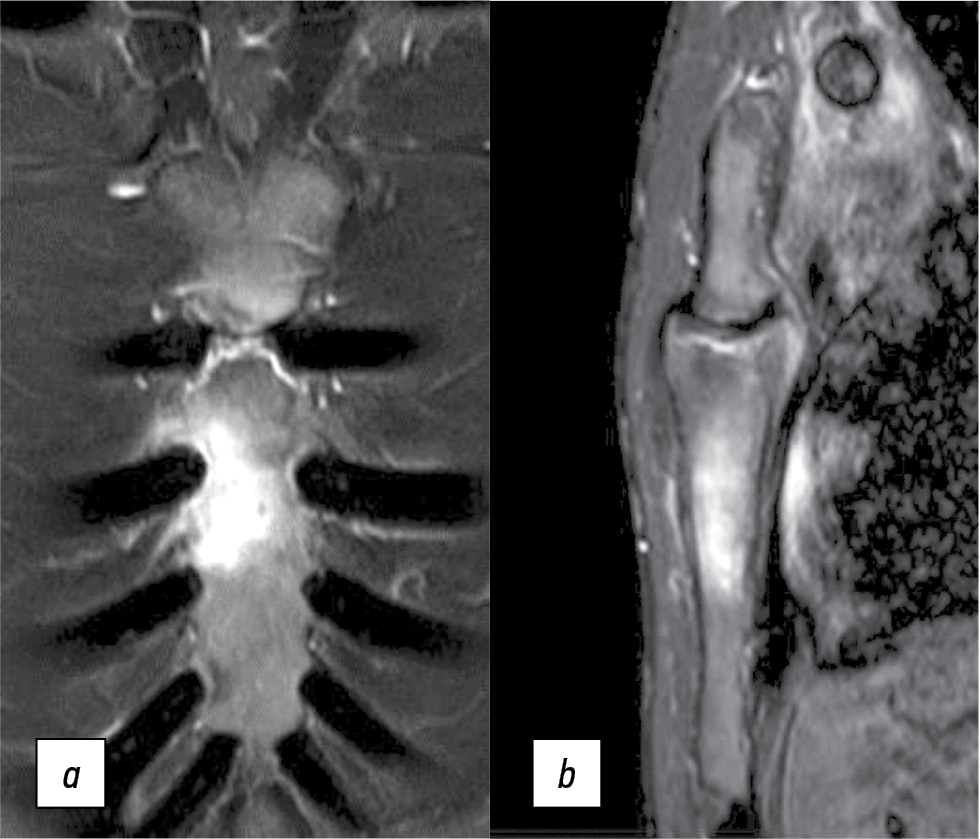

Контрольная МРТ проведена 02.03.2022 (рис. 3). По сравнению с предыдущим исследованием отмечена положительная динамика в виде уменьшения зоны отёка костной ткани тела грудины справа с сохранением активного участка по левой поверхности грудины между III и IV ребрами диаметром до 12 мм (см. рис. 3).

Рис. 3. Магнитно-резонансная томограмма после назначения золедроновой кислоты. PD/FS, коронарный (a) и сагиттальный (b) срезы. Положительная динамика в области пораженной грудины.

Fig. 3. Magnetic resonance imaging after therapy of zoledronic acid. PD/FS, coronal (a) and sagittal (b) partitions. Positive dynamics in the area of the affected sternum.

20.05.2022 выполнена МРТ всего тела в режиме STIR, DWIBS. Повышения интенсивности сигнала не зарегистрировано. На серии STIR, помимо обнаруженного по данным предыдущих исследований воспалительного процесса в области тела грудины, дополнительных участков патологического очагового повышения интенсивности сигнала не выявлено.